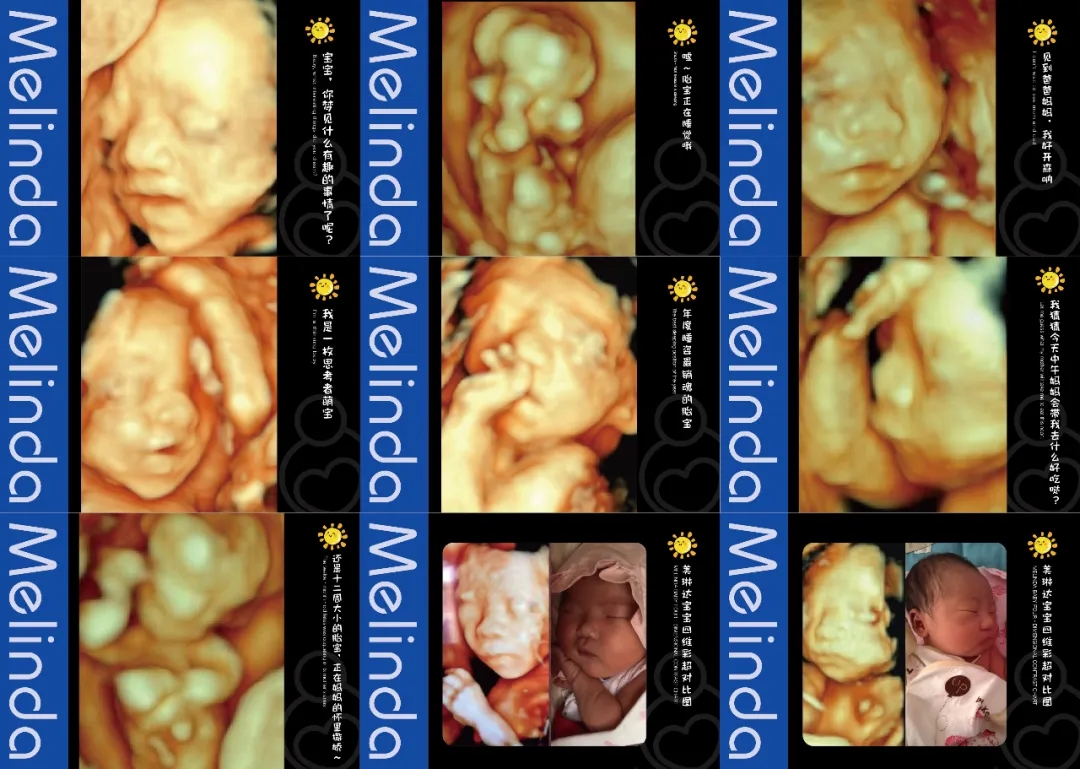

(美琳达四维宝宝照片)